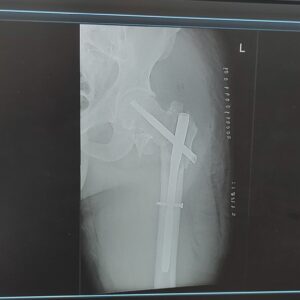

De afgelopen weken waren nogal hectisch. Ik kan nog niet zoveel na m’n operatie, maar er moest wel e.e.a. in en aan het huis gebeuren om het klaar te[…]

Het is onvermijdelijk; We zullen onze plannen aan moeten passen. Kitesurfen gaat nu eenmaal “effe nie”, maar ook een stevige hike wordt natuurlijk nog niks de komende maanden. Ik[…]

De dag na de operatie mag je dan alweer staan / lopen! Wow. Achter een looprekje weliswaar, maar toch. De pennen zijn zo sterk dat de heup 100% belastbaar[…]